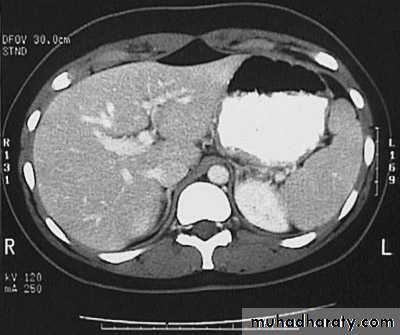

Hydatid cyst

Appear as large oval hypo dense area density of fluid with well defined margin , sometime at their periphery multiple flecks of calcification are seen at their periphery .

Hydatid cyst with daughter cyst , appear as multiple hypo densities rounded area within the main loculi with multiple rim of

calcification

Hydatid cyst within the liver